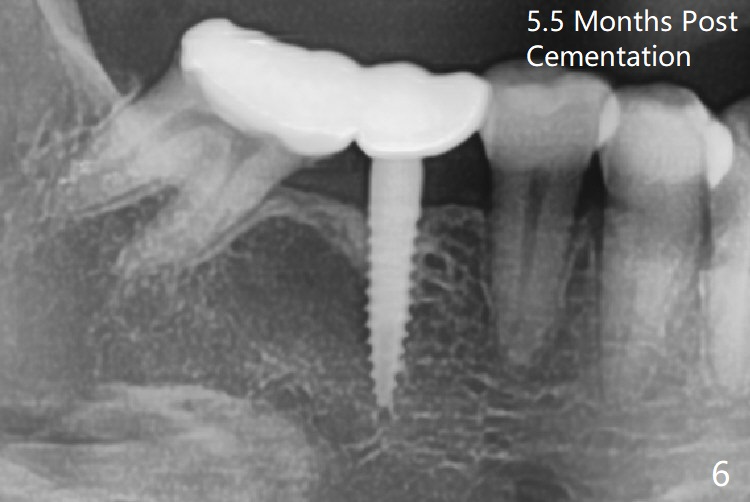

When a 1.2x12 mm drill is placed at #30, it passes the bone cavitation (Fig.1 red dashed line (low density)) twice for two-pointed fixation. So does the 3x12(2) mm 1-piece implant (Fig.2,3). The mesial margin of the tooth #31 is further reduced prior to suturing and periodontal dressing. Impression is taken 5 months postop (Fig.4). Residual cement mesial to the crown at #31 is later removed (Fig.5). Since the crowns were made at #30 and 31 at the same time, there appears no food impaction in between (Fig.6, 5.5 months post cementation).